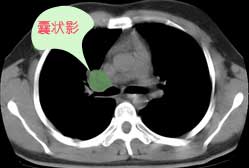

右肺门增大,囊状影与肺动脉分支有关,上叶支气管受压移位。

考虑发生于右肺动脉分支的肺动脉瘤。

鉴别:肺结节病,多侵犯两侧肺门及纵隔淋巴结。